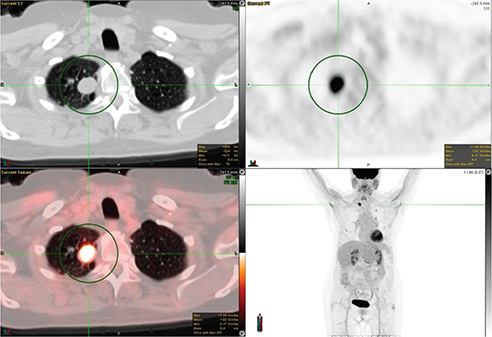

The FDG avidity of lung cancer is mainly dependent on two factors: tumor size, and histology. For nodules greater than 8 mm, 18F-FDG PET/CT has a high negative predictive value in excluding malignancy (20). Squamous cell carcinoma tends to have a higher uptake as shown in Figure 3. Low-grade adenocarcinoma, mucinous adenocarcinoma, colloid carcinoma, and typical carcinoid can have very low FDG avidity. Bronchoalveolar carcinoma (BAC), a well-differentiated subtype tends to have peak SUV (1.5 ± 0.2) lower than all other non-BAC adenocarcinomas (SUV, 3 ±1.5). False positive FDG uptake can be seen in infectious and inflammatory lesions.

Fig 3

Figure 3. Right upper lung mass that was pathologically confirmed as squamous cell carcinoma. FDG PET/CT images include axial CT (top left panel), axial PET (top right panel), fused axial PET/CT (bottom left panel), and maximum intensity projection (MIP) PET image (bottom right panel). In the green circle, there is a lobulated and spiculated right upper lobe mass on CT with intense FDG uptake on PET.